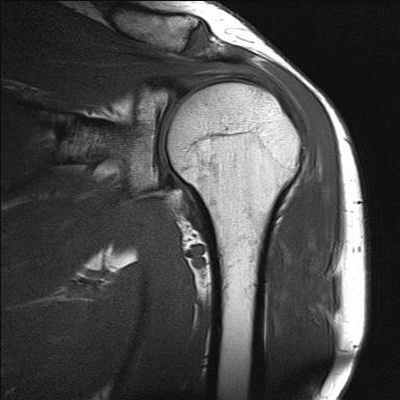

Самыми сложными для диагностики травматических изменений являются коленный и плечевой суставы, так как их строение объединяет много важных внешних и внутрисуставных структур. Обычный метод рентгенографии дает представление о состоянии костей, их форме, размере, соотношении костей внутри сустава, суставной щели, но он абсолютно не информативен для просмотра мягких тканей. Чтобы исключить возможность кровоизлияния внутри сустава после ушиба мягких тканей, применяют такие методы диагностики, как прямая МР артрография и непрямая МР артрография.

Одна из точек приложения метода МРТ установление диагноза при заболеваниях суставов. Чаще всего проводят МРТ коленного сустава, реже других (плечевого, тазобедренного, лучезапястного и голеностопного) и позвоночника. Однако, виды патологии, при которых используют МРТ коленного сустава, напрямую связаны с диагностическими возможностями данного исследования. Основным преимуществом МРТ в травматологии и ортопедии по сравнению с рентгенологическим исследованием и КТ является возможность визуализации мягкотканных структур, в том числе внутрисуставных связок, менисков, синовиальных складок.